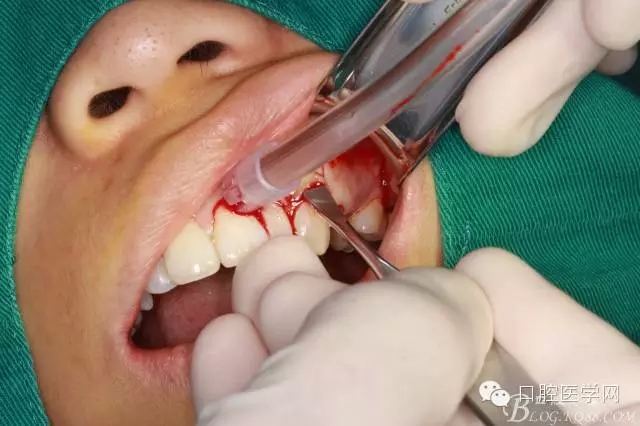

常規(guī)口內(nèi)外消毒鋪巾

局部浸潤麻醉

齦乳頭麻醉

鼻腭神經(jīng)麻醉